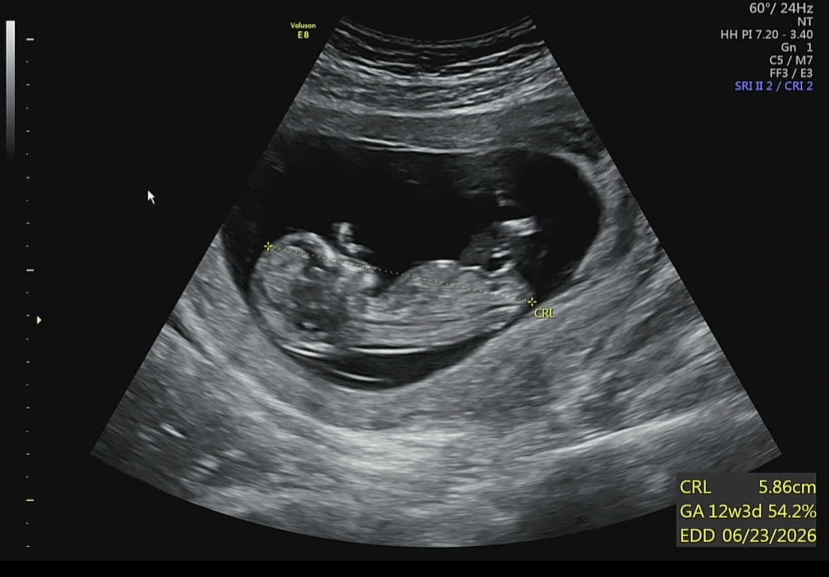

각도법 투표 부탁드려요:)

이전에 글을 썼었는데 투표를 깜빡했지 모예요😭 챗지피티와 베이비빌리AI는 딸일 확률이 높다고 하는데 딸 같나요?ㅎㅎ